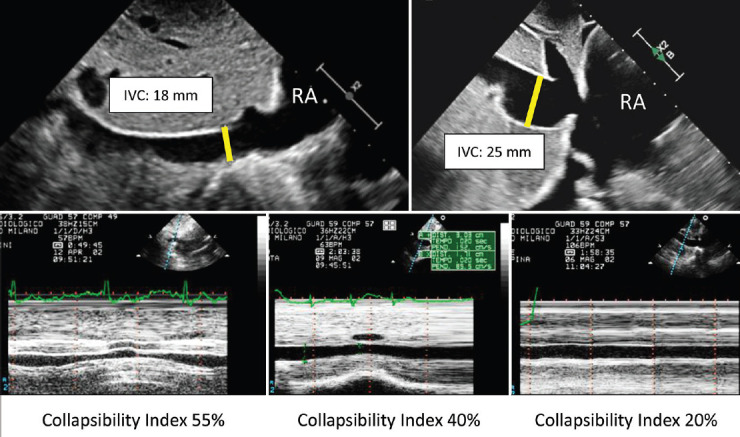

The precise evaluation of pulmonary artery, right atrial, and ventricular pressures is essential for the diagnosis, ongoing management, and therapeutic decision-making in a wide range of cardiovascular conditions, including pulmonary hypertension. Since the early 1980s, the accuracy and consistency of echocardiography in estimating pulmonary artery pressure have been a subject of debate, with multiple formulas developed over time to improve reliability. Despite initial concerns, echocardiography has now been widely accepted as a noninvasive, safe, and readily available alternative to the more invasive right heart catheterization, which remains the gold standard. The growing recognition of echocardiography's role in clinical practice has led to significant advancements in its methodology. This review explores the contribution of echo-Doppler techniques to the assessment of right heart hemodynamics, highlighting their importance in daily practice. It also examines the historical milestones that have facilitated the standardization of various formulas and paved the way for the development of current guidelines. By tracing these developments, the review underscores the relevance of echocardiography in modern cardiology and the importance of continuing to refine its application to ensure accurate and reliable assessments.